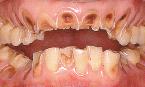

酸蝕症はこのように歯が溶け出して、悲惨なことになりますよ。

早めに来院しましょう。

虫歯以外にも歯が酸によって実質欠損がおきることがあります。

それを酸蝕症といいます。つぎの場合です。

1、塩酸、硫酸などの強酸を取り扱う作業につく労働者

2、拒食、過食などによる嘔吐    胃液によって

3、胃の内容物の逆流によるもの   胃液によって

4、スポーツドリンク、みかん、酢、温泉水の強酸のよるもの

歯が虫歯で黒くなくても。歯が黄ばんでいたり、ゆがんだ形をしていたら早めに来院しましょう。